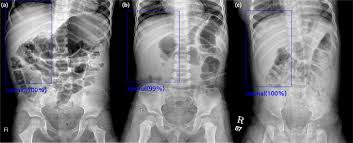

Four different normal abdominal radiographs showing examples of the normal variation in bowel gas pattern. Background, pulse sequences, normal appearance (body mri, abdo mri). Case contributed by dr jeremy jones. Look for normal or abnormal intraluminal and extraluminal gas distribution. Both large and small bowel is demonstrated here and is normal.

Four different normal abdominal radiographs showing examples of the normal variation in bowel gas pattern. Case contributed by dr jeremy jones. It is sometimes abbreviated to axr, or kub (for kidneys, ureters, and urinary bladder). Patil medical college & hospital pune. Again, confirmation with uss or ct is indicated. Repetitive viewing of images will help establish a baseline of normality and normal variation that will represent an internal yard stick for the detection of variation from normal. This is a radiograph of the abdomen of a normal cat that is laying on its right side. Published byerin goodwin modified over 5 years ago. The liver usually displaces the bowel preventing itself from overlying bowel/bowel gas. • fluid levels are abnormal when they are seen in dilated bowel loops or. Organs include the spleen, stomach, and intestines. Medgen uid the evaluation of compliance with irefer guidelines for abdominal imaging and the impact of the normal abdominal radiograph on the clinical confidence and decision making of emergency clinicians. This causes a density on the anteroinferior side on the lateral view which can have many forms.